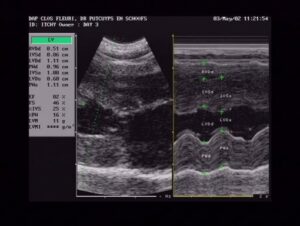

Eerst een korte uitleg wat 2-D en M-Mode betekent:

- 2D betekent twee-dimensionaal; zo zie je het hart alsof er een doorsnede van is gemaakt

- M-mode geeft een beeld alsof je een LIJN door het hart trekt die dan de veranderingen in het hart toont als het samentrekt en ontspant (hoe de wanden dikker en dunner worden). Het toont ook de ‘holte’ in het hart, het ventrikel. Op het scherm zie je in M-Mode allerlei golven die op en neer gaan; als je dit scherm stopzet, kunnen de metingen gedaan worden; in de M-mode is tevens de diastole (ontspanning) en systole (samengetrokken) gemakkelijk te zien (zie volgende pagina voor een voorbeeld hiervan).

De afkortingen:

Eerst hebben we de metingen in diastole (wanneer het hart compleet ontspannen is)

- IVSd: IntraVentricular Septum in Diastole

betekent de meting van het septum tussen de ventrikels (het septum is de wand die het linker ventrikel scheidt van het rechter ventrikel) - LVIDd: Left Ventricle Inner Diameter in Diastole

betekent de grootte van het ventrikel – de holte in het hart. Dit wordt eerst in diastole gemeten, later in systole (meestal in M-Mode) - LVFWd: Left Ventricle Free Wall in Diastole

Dit is de wand van het ventrikel aan de buitenkant van het hart

En nu de metingen in systole (wanneer het hart compleet samengetrokken is)

- IVSs: IntraVentricular Septum in Systole

betekent de meting van het septum tussen de ventrikels (het septum is de wand die het linker ventrikel scheidt van het rechter ventrikel) - LVIDs: Left Ventricle Inner Diameter in Systole

betekent de grootte van het ventrikel – de holte in het hart. Dit wordt eerst in diastole gemeten, later in systole (meestal dan in M-Mode) - LVFWs: Left Ventricle Free Wall in Systole

dit is de wand van het ventrikel die aan de buitenkant van het hart ligt

- SF: Shortening Fraction (uitgedrukt in %)

Dit is de berekening van de samentrekkingen van het hart uitgedrukt in procent. Het wordt berekend door het verschil tussen LVIDd en LVIDs (die reeds gemeten zijn) te delen door LVIDd. Dit percentage geeft aan hoeveel percent het ventrikel verkleind in systole vergeleken met wanneer het in diastole is.

Note: de samentrekkingen zijn minder krachtig als de kat onder verdoving is. - Ao: aorta

De diameter van de aorta wordt gemeten. Het bloed stroomt via het ventrikel in de aorta en voorziet zo het lichaam met zuurstofrijk bloed. - LA: left atrium – linker atrium

De diameter hiervan wordt gemeten.

Ao en LA worden altijd in 2-D Mode gedaan. - LA/Ao: betekent LA gedeeld door Ao

Deze berekening geeft de subjectieve grootte aan van het linker atrium, dwz me vergelijkt de grootte van het linker atrium met de grootte van het hart in zijn geheel.Deze twee (LA en Ao) zijn normaal ongeveer hetzelfde in grootte. Meestal is de verhouding ietsje groter dan kleiner (dus 1, 1.2 en 1.3 zijn nog normaal; wanneer het meer dan 1.4 wordt is er reden tot ongerustheid). - Subjective Left Atrial Size: Subjectieve grootte van het linker atrium

Er zijn geen duidelijke afspraken gemaakt over de grenzen hier, voor zover ik weet, maar een vergroot atrium kan een teken zijn van HCM of RCM. - SAM: Systolic Anterior Motion of the Mitral Valve

Als de mitralislep – die verondersteld wordt om helemaal te sluiten – zich niet helemaal sluit, kan je abnormale bloedstroming krijgen, turbulenties en lekken. Dit wordt meestal veroorzaakt doordat er een lokale verdikking is van het septum waar de mitralisklep (het dichtst bij de aorta) dan blijft aan kleven. De kleppen kunnen dan open blijven staan zodat het bloed niet volledig uit het ventrikel geperst wordt tijdens het samentrekken en terug zal lekken in het linker atrium. Dat is dan ook de oorzaak waarom SAM leidt tot een vergroot linker atrium.

Bij autopsie kan men soms de lesies (littekens) zien die veroorzaakt zijn door de constante terugslag van de mitralisklep tegen de wand – SAM! Hierdoor kan SAM soms zelfs bij autopsie aangetoond worden. - End systolic Cavity Obliteration:

Dit betekent dat er geen ruimte meer is in de linker hartkamer (ventrikel) tijdens de systolische fase – als het hart dus samentrekt. Dit wordt veroorzaakt door een verdikking van de hartwand of verdikte papillair spieren. In een normaal hart is er altijd nog wat ruimte over. De hartwand verdikt aan de binnenkant van het hart, niet aan de buitenkant. - Papillary muscles: Papillair spieren

In de hartwand van de linker- en rechterventrikels zitten spieren die verbonden zijn aan touwtjesachtige vezels of ‘draden’ die op hun beurt vastzitten aan het andere eind aan mitralisklep. Deze draden zien er op het scherm uit als witte lijnen. De papillair spieren kunnen verdikt zijn, maar kunnen ook langer zijn dan normaal het geval is. Dit kan soms verward worden met verdikkingen maar heeft daar niets mee te maken. Sommige katten kunnen ook gespleten papillair spieren hebben, evenals extra kleine. Dit schijnt geen effekt te hebben op de katten, in tegenstelling tot verdikte papillair spieren.